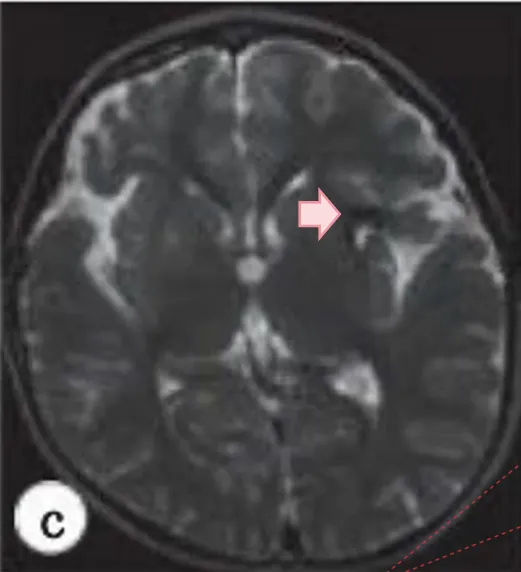

然而一个月后再检查,病变已经扩大并压迫到周围的脑组织(图4a-c)。尽管桃子依旧无明显症状,但预计病变还会进一步扩大,进而产生神经症状。

图4(a)(b):二次术后随访MR发现,左侧岛叶病灶长大了两倍以上,明显水肿。

图4(c):术后MRI显示手术瘢痕组织,而不是术前异常肿块。

术中未发现任何动脉瘤或血管异常,血肿最终被清除(图4d-e)。术后桃子恢复良好,无后遗症。术后一年核磁复查显示术前血肿消失。

图4:(d)搭桥术后脑MRA显示肿块形成;(e)术后MRA显示的大肿块在消失。